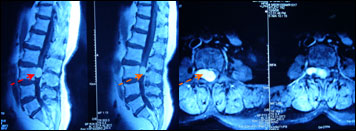

腰椎管内神经鞘瘤

女性,63岁,右腰臀部疼痛3月。查体:右侧L4-5分布区针刺痛觉减退。

术前图片:

手术全切肿瘤,术后患者疼痛缓解,顺利出院。

专家评点:马尾是神经根的组合,该处神经鞘瘤多发,手术难度不大。手术可切实解决患者的病痛,明显改善生活质量。